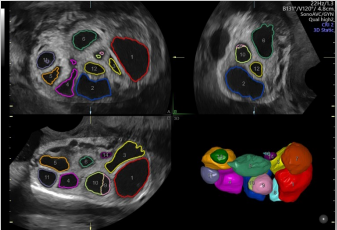

卵泡自動監(jiān)測

能夠自動計算受激卵泡數(shù)量和體積并排序,幫助快速識別優(yōu)勢卵泡。

通過自動的放置取樣框綠線并根據(jù)胎兒活動自動調(diào)節(jié),使得容積圖像的獲取更簡單快速。